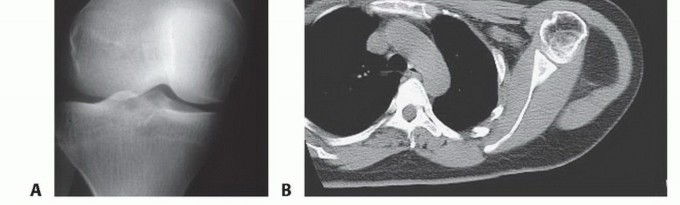

Clinical & Radiographic Imaging